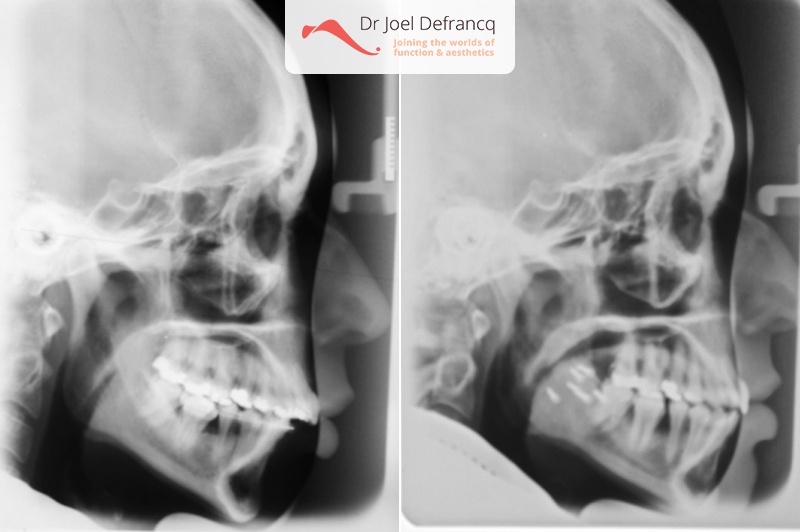

Diagnose van het gezicht

- Te kleine onderkaak (Overbeet)

- Overbeet, weke kin.

Dentale diagnose

- Klasse II divisie 1

Kaakchirurgie

- Onderkaak naar voren.